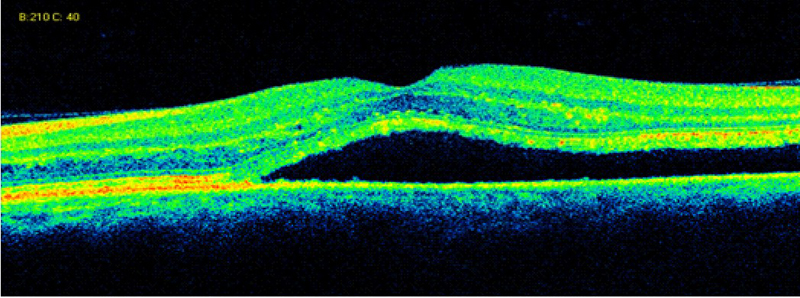

Membrana epiretiniana

La formación de membrana epiretiniana (MER) en asociación con los procesos inflamatorios intraoculares y con el edema macular uveítico es una complicación estructural relativamente frecuente. La OCT ha permitido mejorar la capacidad para detectar MER y describir sus efectos morfológicos sobre la retina. En la OCT, la MER aparece como una línea hiperreflectiva adherida a la retina. La OCT demuestra en los pacientes con uveítis un alto porcentaje de MER en comparación con las observadas oftalmoscópicamente. En gran parte de los casos con MER detectados por oftalmoscopia, la OCT revela también la presencia de tracción vitreoretiniana. De esta forma se confirma que la OCT tiene una alta sensibilidad para detectar la presencia de MER y anormalidades vitreoretinianas en el área macular, sugiriendo que el mecanismo traccional podría ser uno de los mecanismos etiopatogénicos del comienzo del edema macular en la uveítis (

Figura 9).

Figura 9. Edema macular quístico y traccional con presencia de membrana epiretiniana.